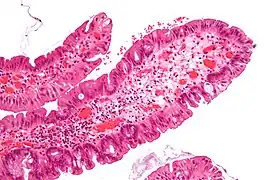

| Traditional serrated adenoma with intermediate magnification, showing serrated crypts and cytologic atypia (H&E stain). | |

Traditional serrated adenomas are characterized by ectopic crypts, pseudostratification, and a villous pattern with stretched nuclei.[3]